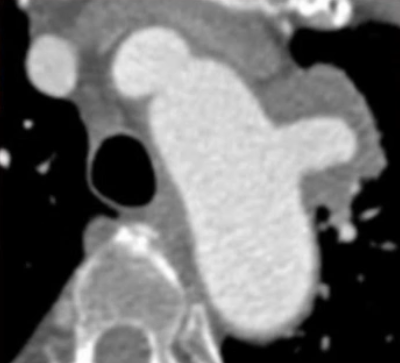

术前检查与评估

增强CTA显示,主动脉弓前壁假性动脉瘤深约2.23cm,基底宽约3.34cm。瘤体已累及左侧锁骨下动脉,且距左颈总动脉仅约4mm,距无名动脉约19.7mm。检查结果表明,该病例需要将覆膜区放置在无名动脉后,同时重建左锁骨下动脉和左颈总动脉,以恢复正常的血管通路,避免脑部供血不足等严重并发症的发生。

术前CTA